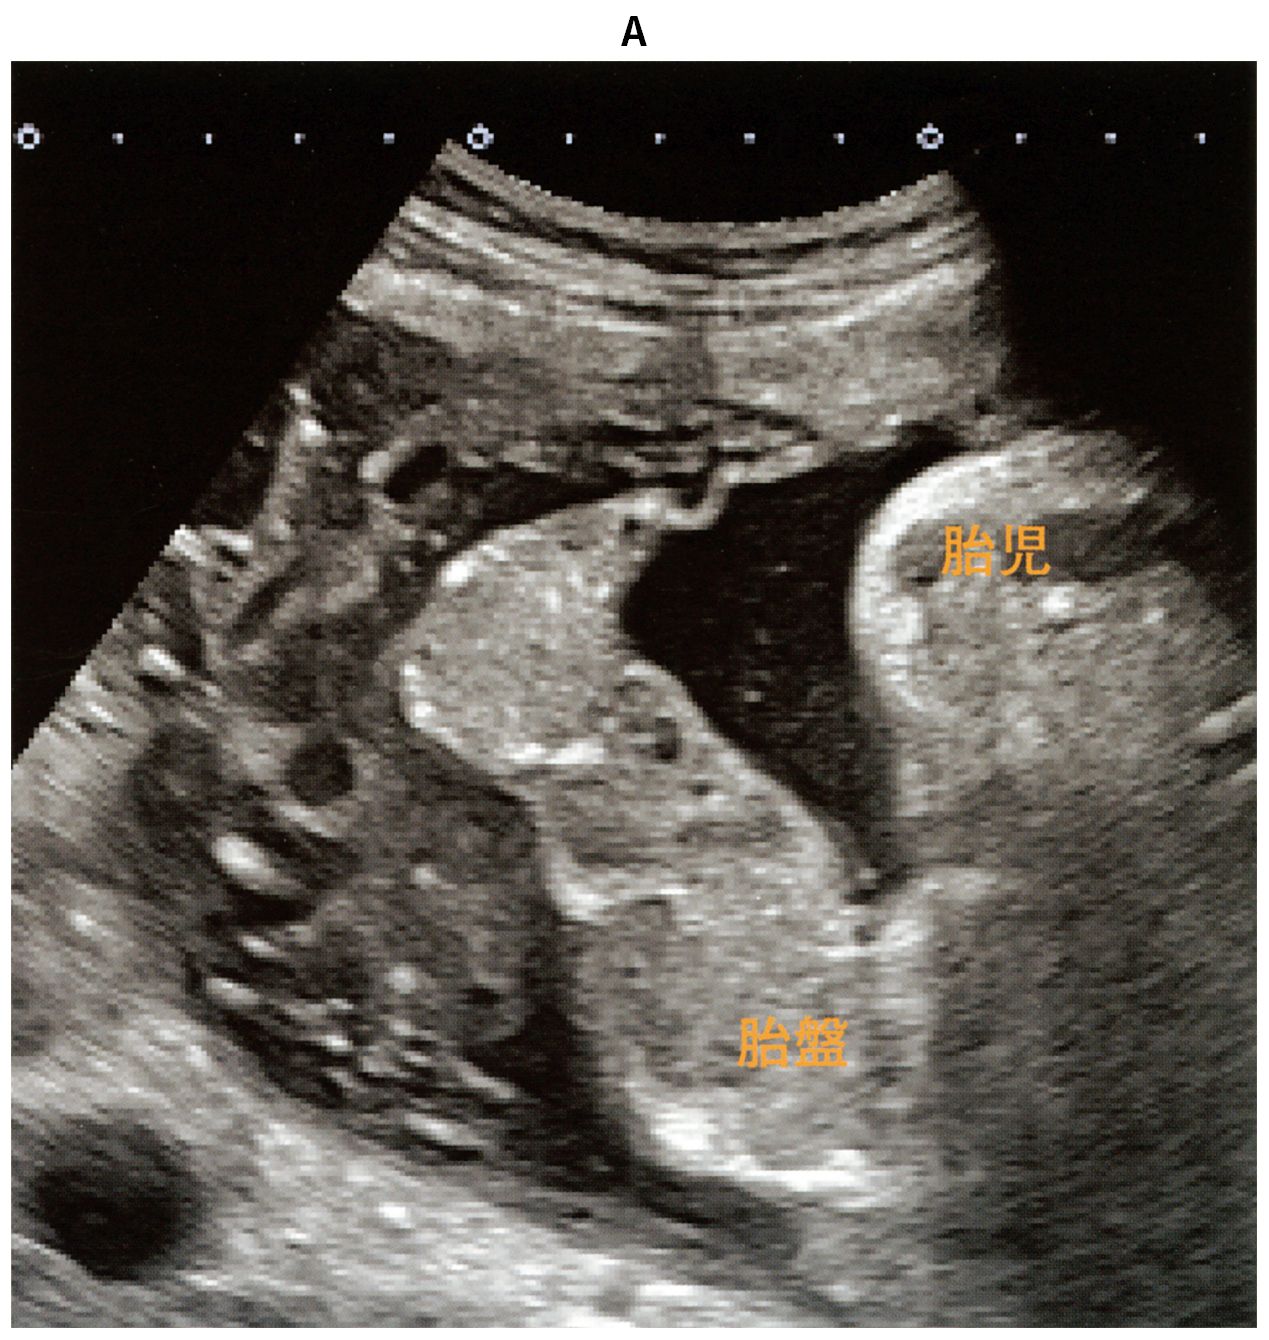

40歳の初妊婦(1妊0産)。妊娠33週0日,持続する下腹部痛と頭痛を主訴に来院した。既往歴に特記すべきことはない。喫煙は25歳から現在まで10本/日。血圧154/98mmHg。腟鏡診で少量の出血を認め,子宮口は3cm開大している。尿蛋白3+。経腹超音波像(A)と胎児心拍数陣痛図(B)とを下に示す。帝王切開を施行する方針とした。

帝王切開の適切な施行時期はどれか。